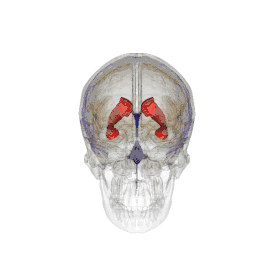

Проекция желудочков головного мозга на его поверхность.